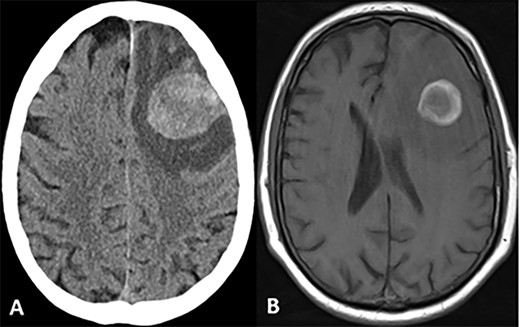

CASE

MRI scans indicating new metastatic lesions of the bilateral frontal lobes and right cerebral peduncle.